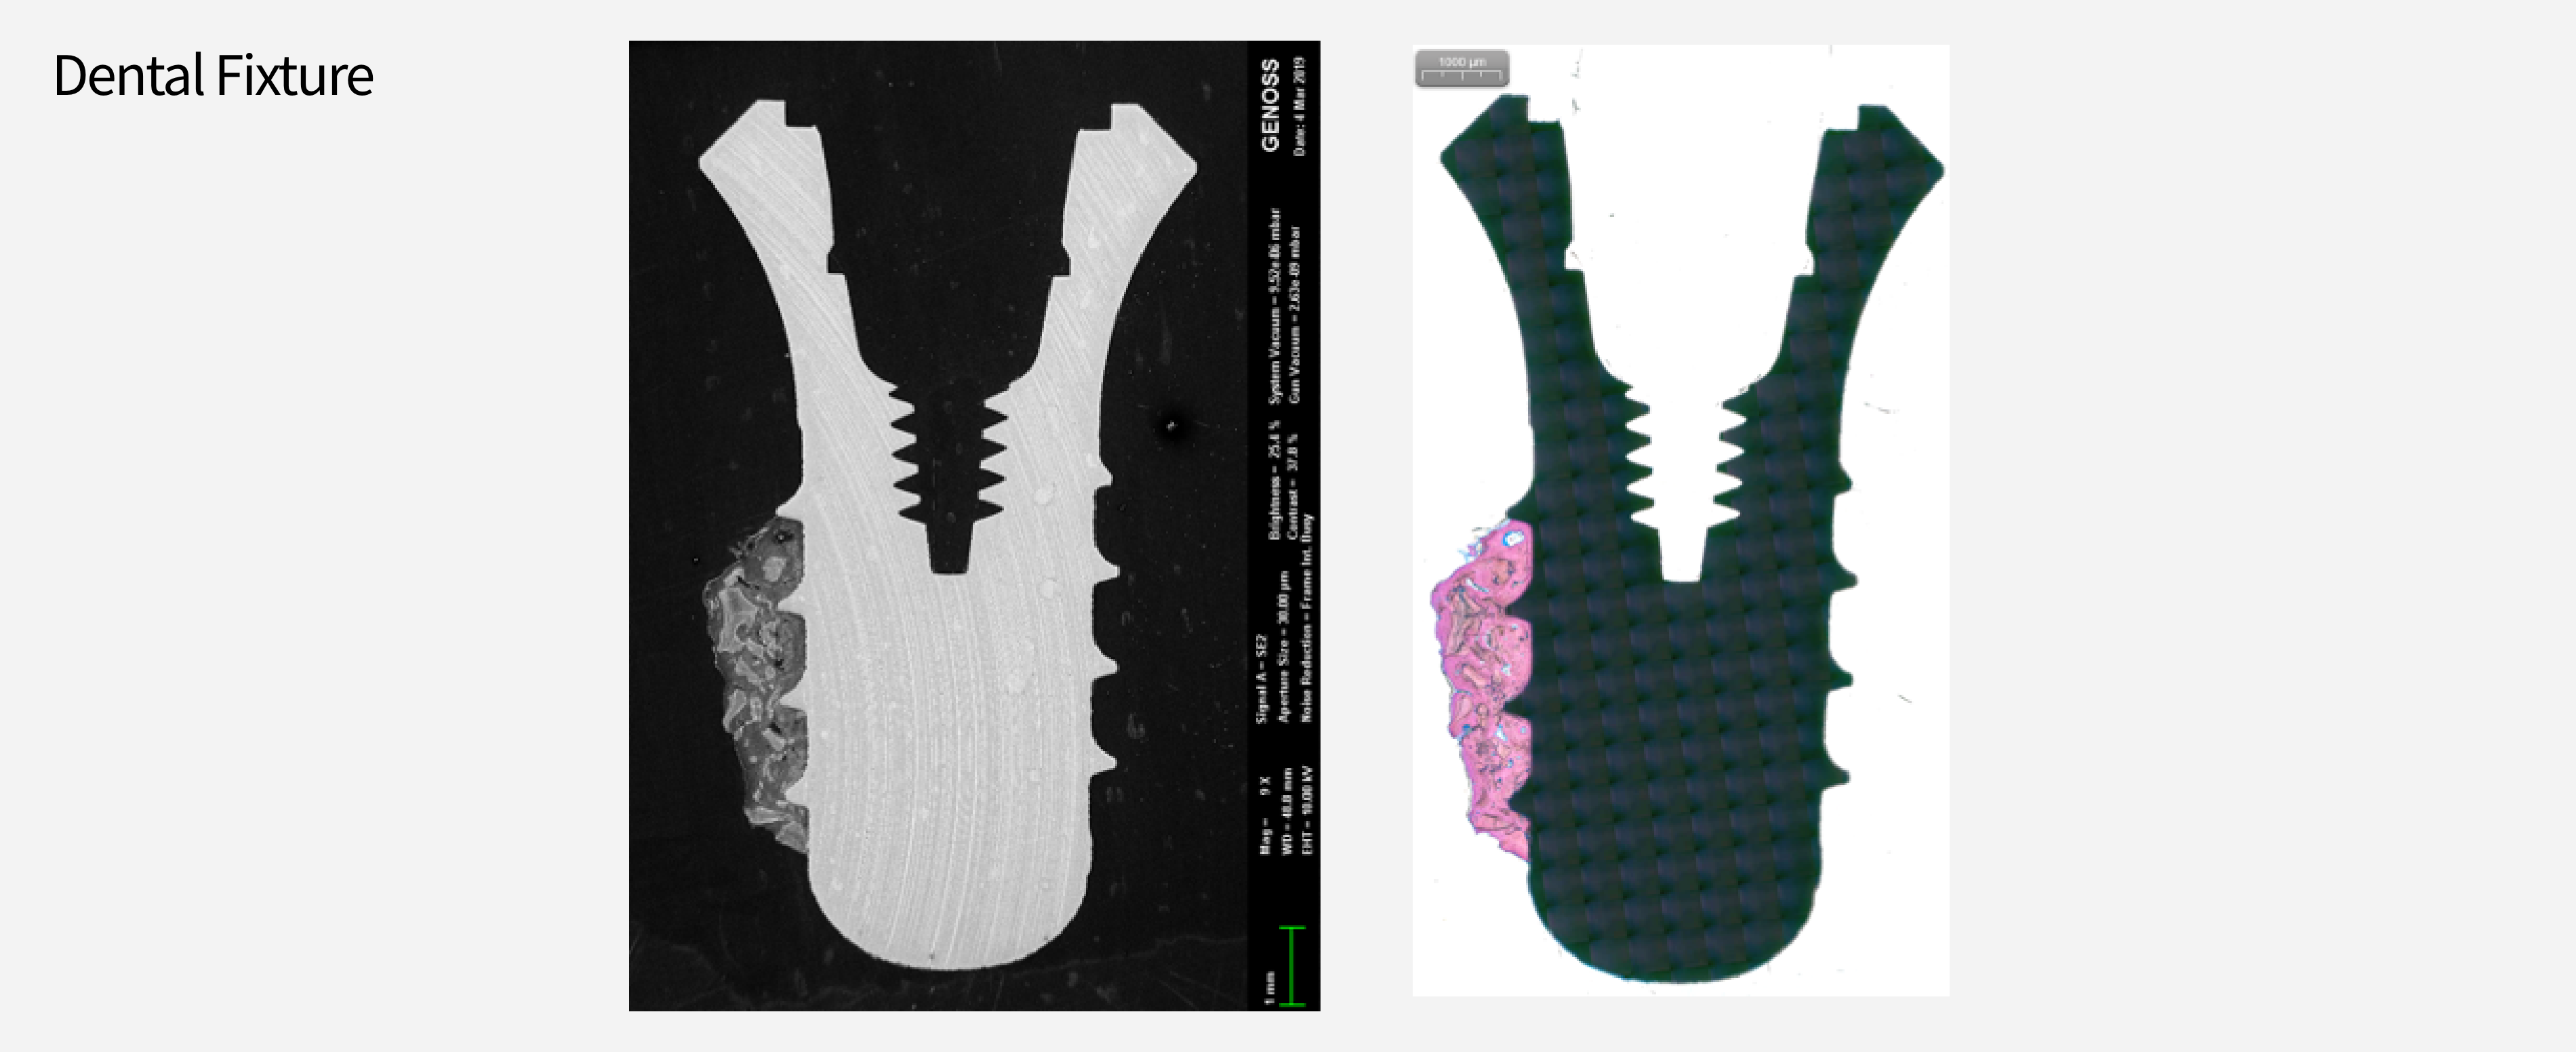

분석 예시

장비

이미지

2D & 3D 이미지 및 정량분석

Implant 체결 구조 분석

Implant

FE-SEM

Sigma 500

Zeiss, Germany